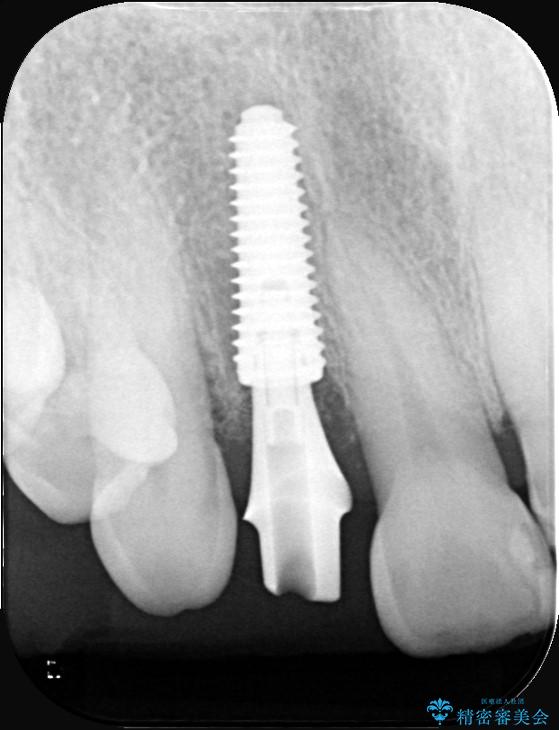

インプラント治療は、低侵襲で短期間に行える「抜歯即時インプラント治療」を選択しました。

この方法は、抜歯したその日にインプラントを埋入し、手術が1回で済むのが大きな特徴です。

治療期間も短く、抜歯からわずか3か月でオールセラミッククラウンを装着することができます。